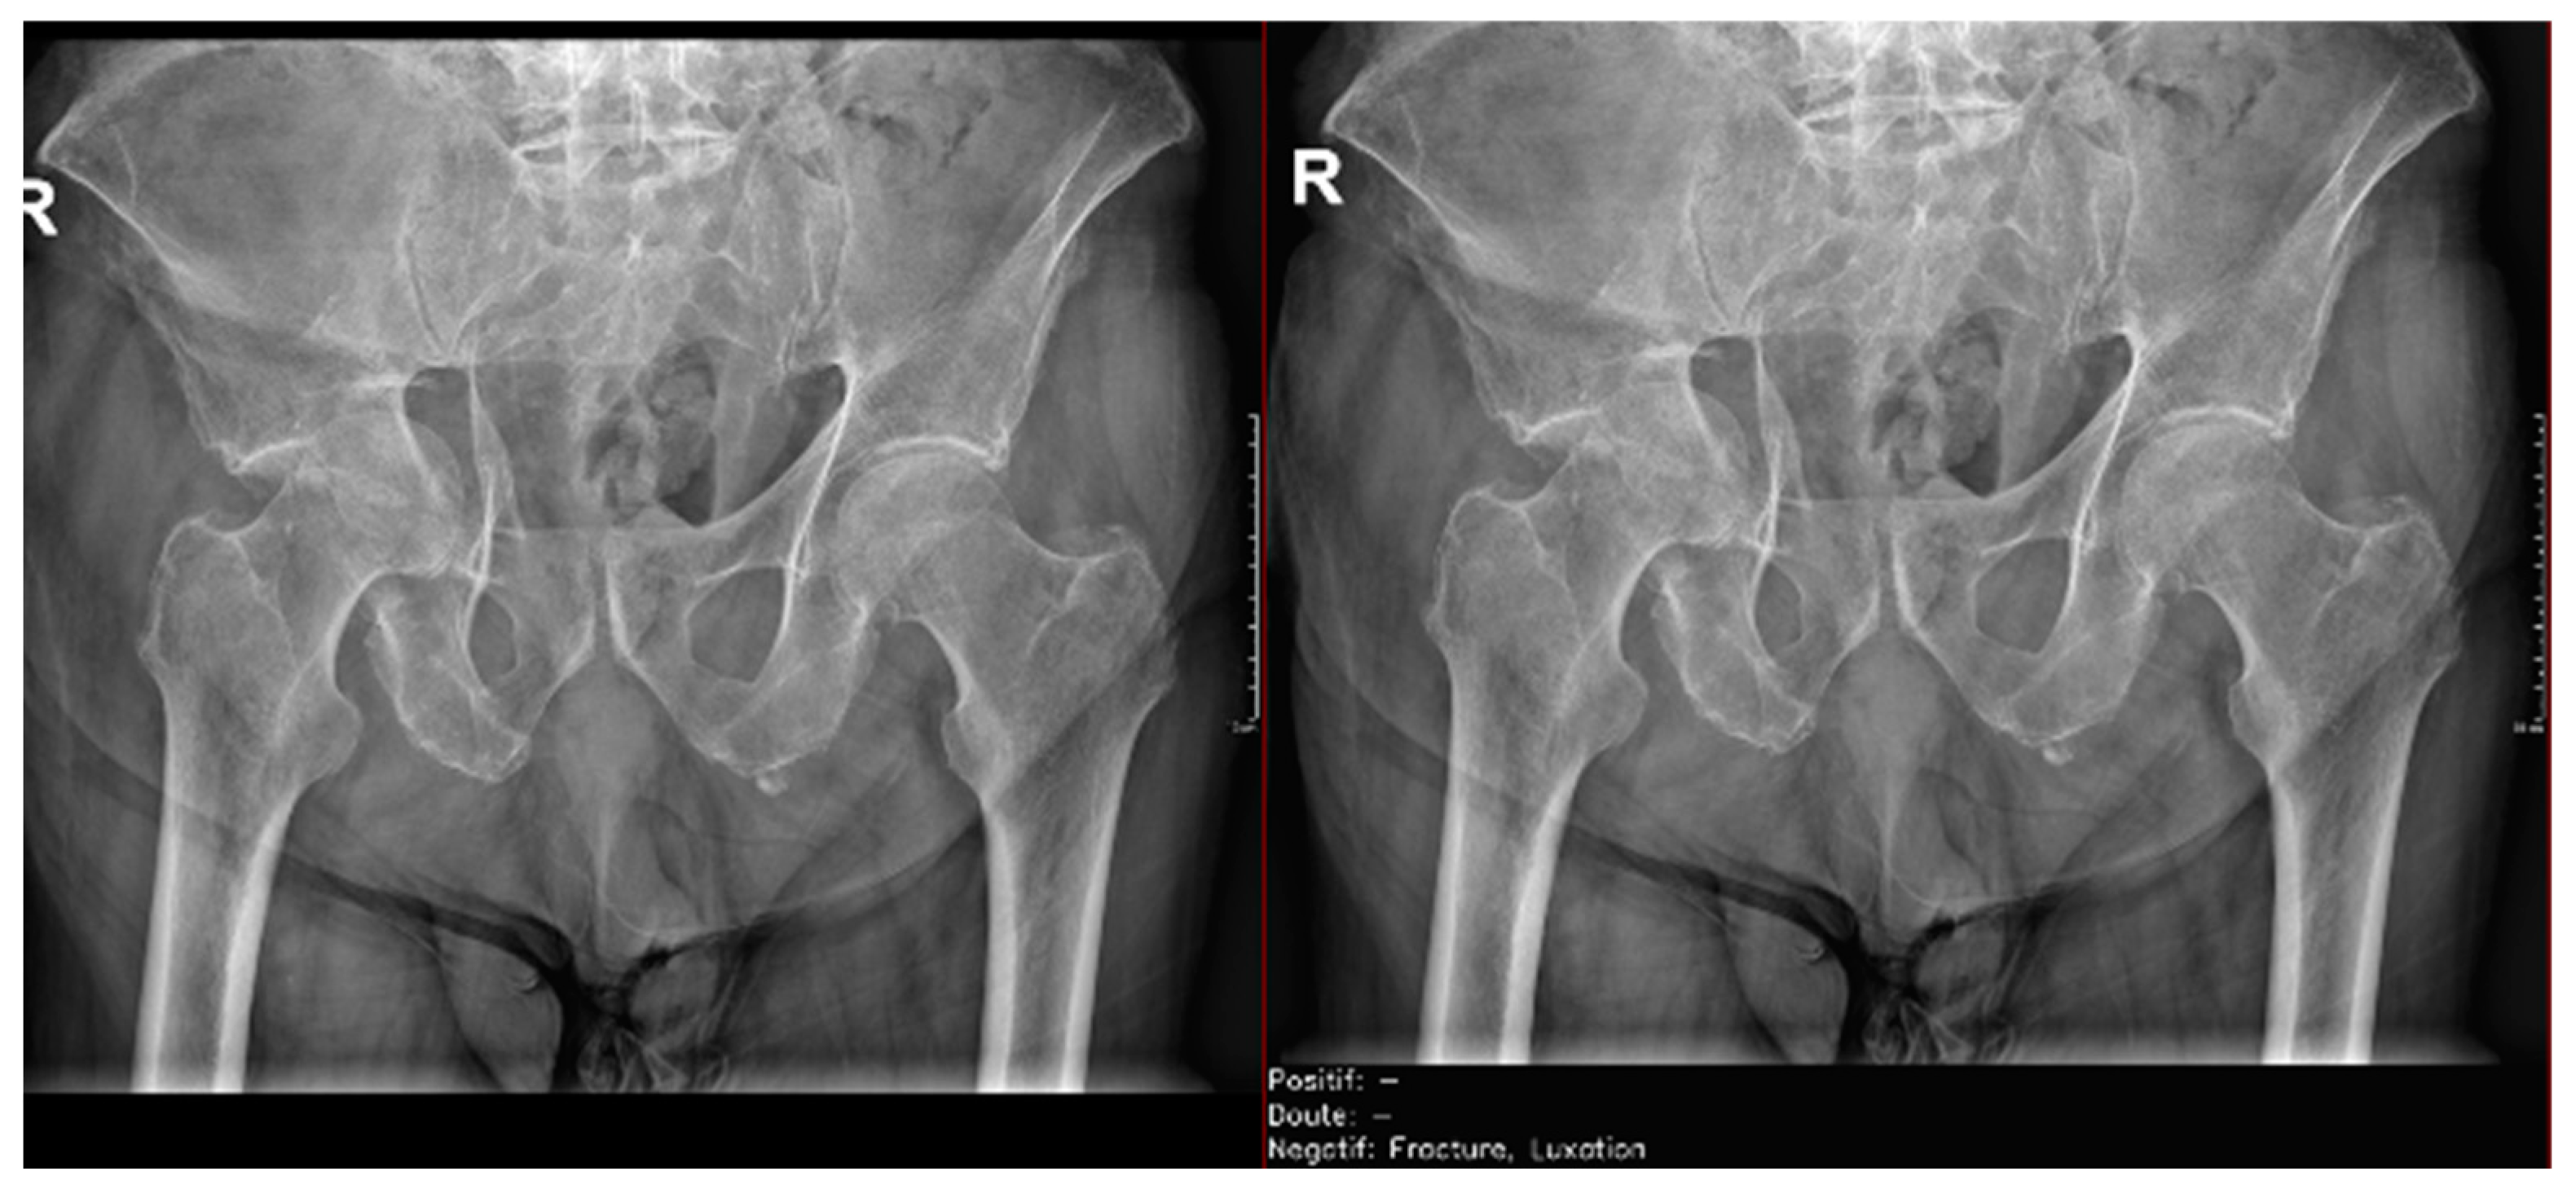

Regarding the detection of dislocations (Table 4), we observed better sensitivity results in the resident’s reading compared to that of the AI, with a high sensitivity of 77.8% in the overall cases, which improved to 84.6% in the large joint group. In contrast, the AI showed lower sensitivity values, with 35% in the overall cases and 35.7% in the large joints. However, specificity values were excellent for all readings and groups, reaching between 99.5% and 100%. (Figure 9 and Figure 10).

Figure 9.

Glenohumeral joint dislocation that was correctly recorded by both the AI and radiology resident.

Figure 10.

Pelvic fracture and coxofemoral dislocation, which was recorded as negative by AI but correctly detected by the radiology resident.